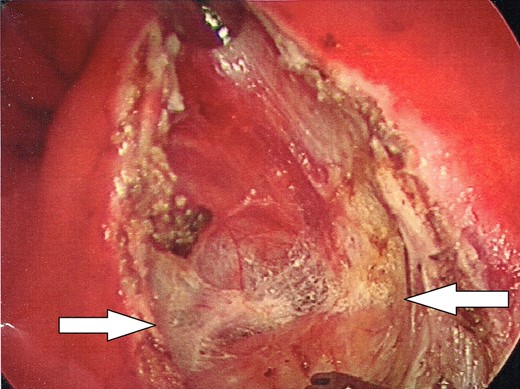

Once the dissection plane was entered, insufflation of the perirectal extraperitoneal space allowed for excellent exposure for a combination of blunt and Harmonic Scalpel dissection (Figs 4 and 5).

Enlargement of the proctotomy. The plane of dissection is visible (indicated by arrows), with the dome of the cyst seen at the bottom of the image.